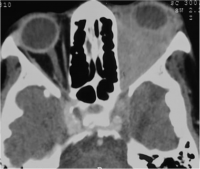

Sub Periosteal Abscess. Coronal contrast-enhanced CT image of right orbit showing extraconal marginally enhancing fluid collections located superonasally, consistent with subperiosteal abscess. These are present in continuation with opacified right ethmoidal air cells and right maxillary antrum with soft tissue density with hyperdense content. |

| Sub periosteal abscess[14] | No age/gender predilection | Collection of subperiosteal fluid causing abaxial proptosis along with other signs of cellutlitis | CT- shows hypodense, convex collection with ring enhancement present along orbital wall